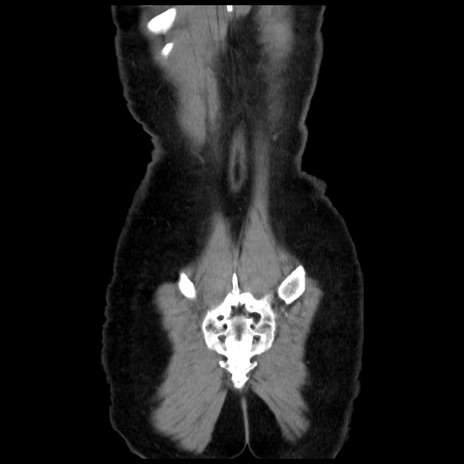

矢状断像